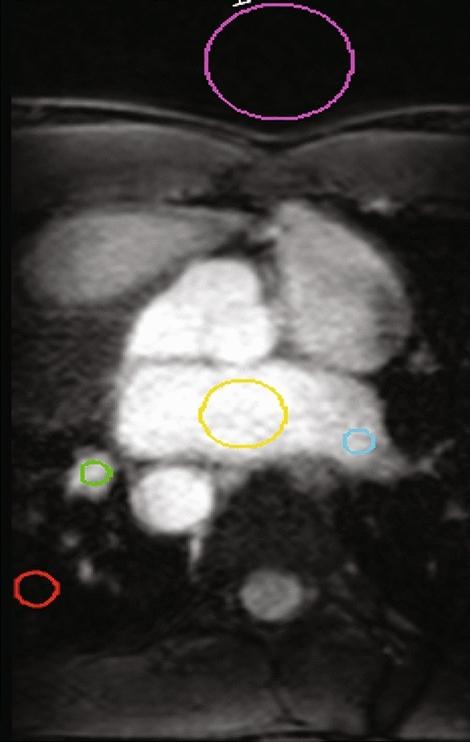

Magnetic resonance imaging (MRI) guided cardiac radioablation (CR) for atrial fibrillation (AF) is a promising treatment concept. However, the visibility of AF CR targets on MRI acquisitions requires further exploration and MRI sequence and parameter optimization has not yet been performed for this application. This pilot study explores the feasibility of MRI-guided tracking of AF CR targets by evaluating AF CR target visualization on human participants using a selection of 3D and 2D MRI sequences.MRI datasets were acquired in healthy and AF participants using a range of MRI sequences and parameters. MRI acquisition categories included 3D free-breathing acquisitions (3D), 2D breath-hold ECG-gated acquisitions (2D), stacks of 2D breath-hold ECG-gated acquisitions which were retrospectively interpolated to 3D datasets (3D), and 2D breath-hold ungated acquisitions (2D). The ease of target delineation and the presence of artifacts were qualitatively analyzed. Image quality was quantitatively analyzed using signal-to-noise ratio (SNR), contrast-to-noise ratio (CNR) and non-uniformity. Confident 3D target delineation was achievable on all 3D datasets but was not possible on any of the 3D datasets. Fewer artifacts and significantly better SNR, CNR and non-uniformity metrics were observed with 3D compared to 3D. 2D datasets had slightly lower SNR and CNR than 2D and 3D datasets. AF CR target visualization on MRI was qualitatively and quantitatively evaluated. The study findings indicate that AF CR target visualization is achievable despite the imaging challenges associated with these targets, warranting further investigation into MRI-guided AF CR treatments.

磁共振成像(MRI)引导下的心房颤动(AF)心脏射频消融术(CR)是一个很有前景的治疗概念。然而,AF CR靶点在MRI图像上的可视性仍需进一步探索,且针对该应用的MRI序列和参数优化尚未开展。这项初步研究通过使用一系列3D和2D MRI序列评估人类受试者的AF CR靶点可视化情况,探讨MRI引导下追踪AF CR靶点的可行性。使用一系列MRI序列和参数,在健康受试者和AF患者中采集MRI数据集。MRI采集类别包括3D自由呼吸采集(3D)、2D屏气心电图门控采集(2D)、将回顾性插值的2D屏气心电图门控采集堆叠成3D数据集(3D)以及2D屏气非门控采集(2D)。对靶点勾画的难易程度和伪影的存在情况进行定性分析。使用信噪比(SNR)、对比噪声比(CNR)和不均匀性对图像质量进行定量分析。在所有3D数据集上都能实现可靠的3D靶点勾画,但在任何3D数据集上都无法实现。与3D相比,3D观察到的伪影更少,SNR、CNR和不均匀性指标明显更好。2D数据集的SNR和CNR略低于2D和3D数据集。对MRI上的AF CR靶点可视化进行了定性和定量评估。研究结果表明,尽管与这些靶点相关的成像存在挑战,但AF CR靶点可视化是可以实现的,这值得对MRI引导的AF CR治疗进行进一步研究。